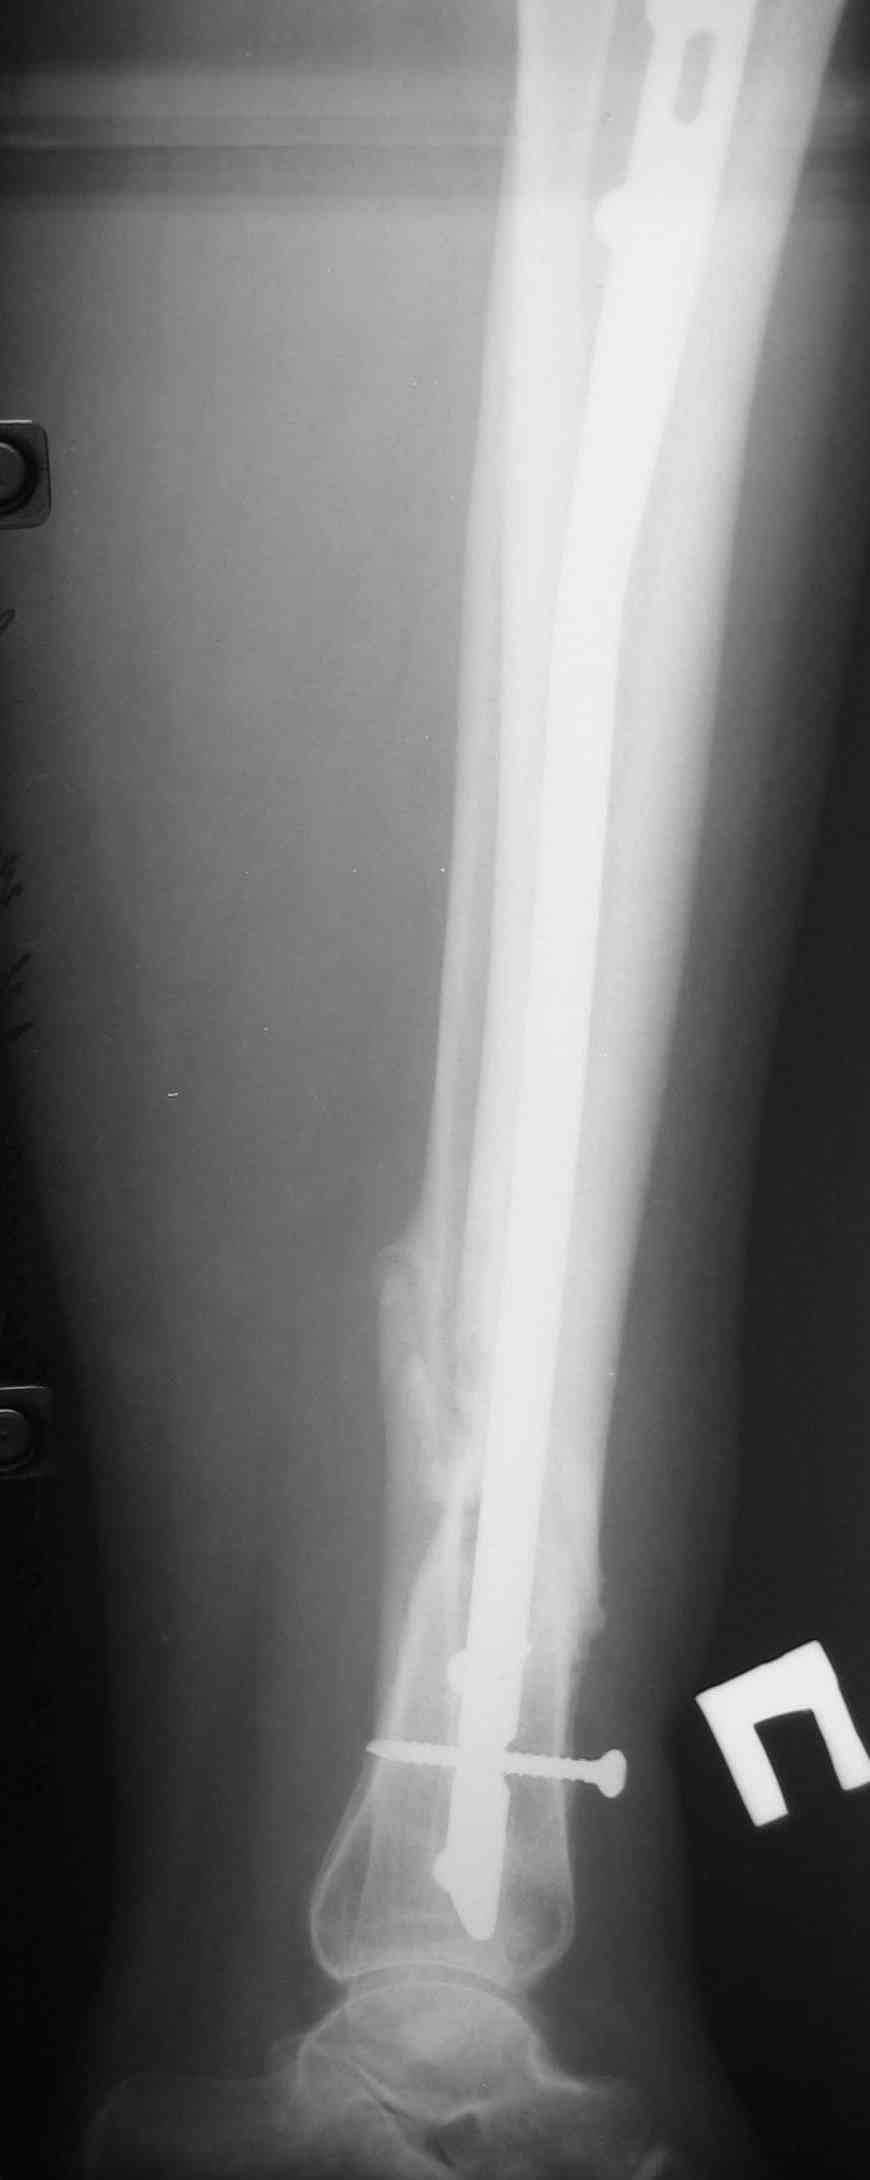

[Ortho] Ложный сустав голени перелом штифта

Р-граммы по теме прилагаю

Имя     : А.jpg